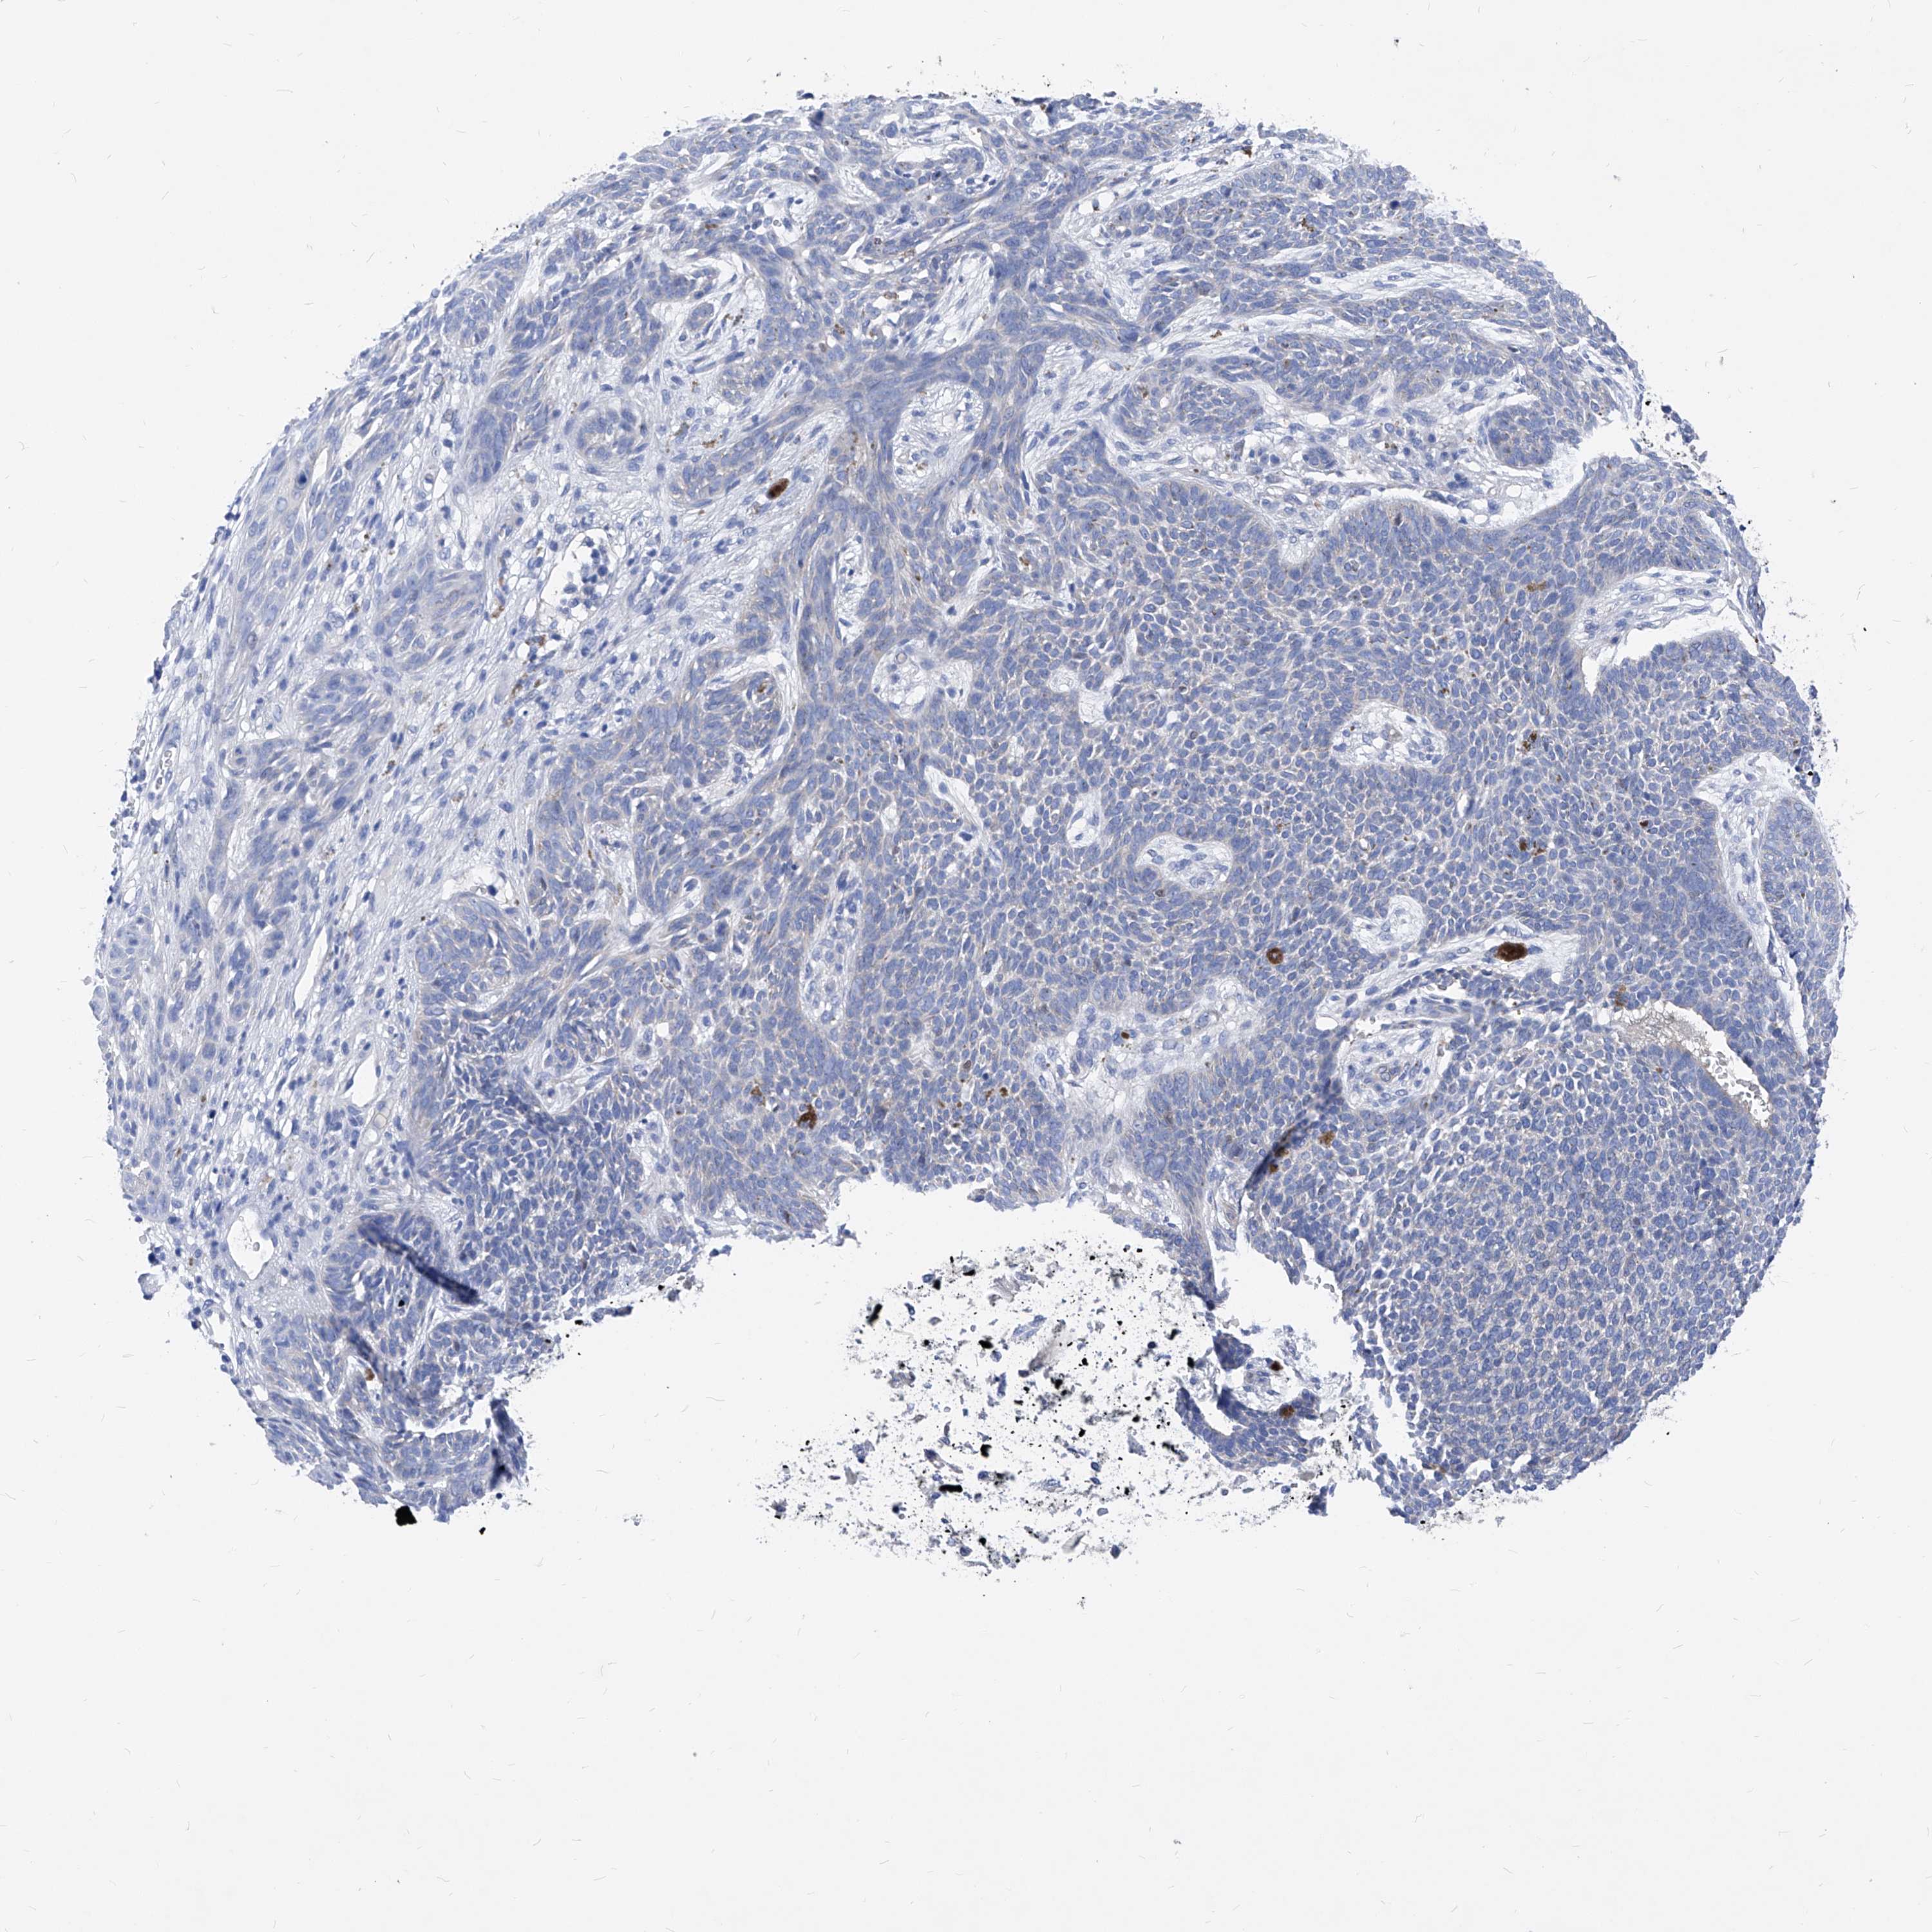

SKIN CANCER - Protein expressioni

A mouse-over function shows sample information and annotation data. Click on an image to view it in a full screen mode. Samples can be filtered based on level of antibody staining by selecting one or several of the following categories: high, medium, low and not detected. The assay and annotation is described here.

Antibody stainingi

Antibody staining in the annotated cell types in the current human tissue is reported as not detected, low, medium, or high, based on conventional immunohistochemistry profiling in selected tissues. This score is based on the combination of the staining intensity and fraction of stained cells.

Each image is clickable and will lead to virtual microscopy that enables deeper exploration of all samples and also displays staining intensity scores, fraction scores and subcellular localization as well as patient and tissue information for each sample.

HPA030419

HPA030420

HPA030422

CAB025196

CAB080286

CAB080287

Basal cell carcinoma

Squamous cell carcinoma, NOS

Squamous cell carcinoma, metastatic, NOS